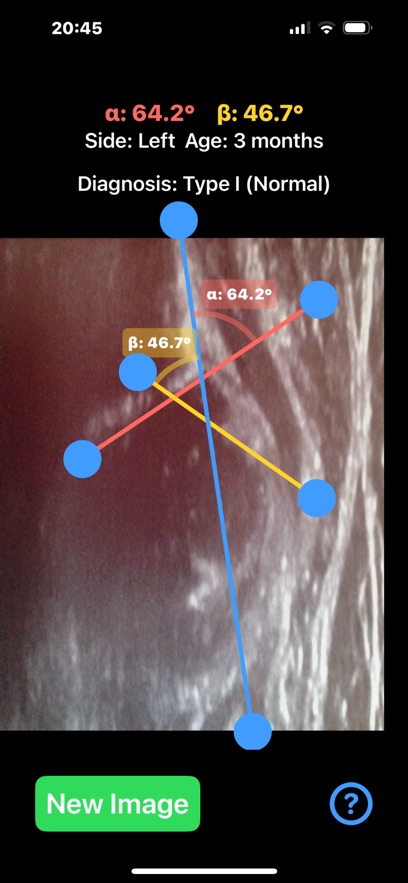

Ultrasonography, rather than X-ray, is the preferred method for diagnosing DDH in infants, especially under the age of 6 months. Ultrasound provides a non-invasive and radiation-free way to visualize the soft tissues, cartilage, and bones in real time. The Graf method is the most widely used technique, where two critical angles—alpha (α) and beta (β)—are measured to assess the development of the acetabulum and classify the hip's condition.This application is designed to aid healthcare professionals—especially radiologists, orthopaedic surgeons—in evaluating DDH by calculating the alpha (α) and beta (β) angles quickl from saved ultrasound images of the patient hip.

Provide instant visual feedback by color-coding the angles:Alpha angle (α): red, Beta angle (β): yellow. Automatically also classify the hip joint based on the Graf method Type I,Type IIa/b,Type IIc,Type III, helping clinicians to have a quick glimpse and visualise the relationship between the angles ,real time.Healthcare professionals, particularly in busy departments, can save significant time by quickly loading ultrasound images and automating angle calculations, identify abnormal hips on the go . App can also be used as a training tool for medical students, residents, and junior clinicians, teaching them how to recognise key landmarks, make accurate measurements, and classify DDH using ultrasound images. By rapid visually displaying the measurements on the screen and generating easy-to-understand images, app helps clinicians explain the condition and its severity to parents.

App offers α and β angle measurement by dragging points on the ultrasound image to key anatomical landmarks, forming lines that define the acetabular roof and cartilaginous roof. The app automatically calculates the angles and classifies the hip condition based on these measurements in real-time.

Important feedback that help allow the user to adjust draggable points and see immediate changes in the angle values helping to fine-tune the position of the lines and target the preferred anatomical landmarks of the ultrasound image more efficiently. User-friendly interface, and reliable classification system based on Graf’s classification that streamline the diagnostic process, and improved overall workflow in clinical practice.